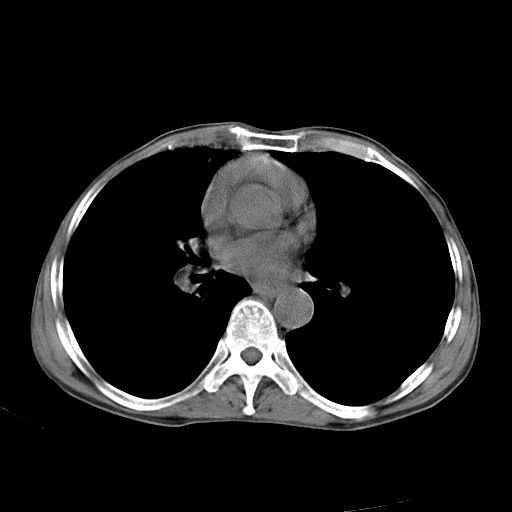

以下是引用苯小孩在2007-5-24 12:47:00的发言:[br]右侧肺门处不均匀密度软组织块影,远端肺组织见斑片模糊影,纵隔内淋巴结明显肿大,边界不清.<纵隔窗第12层面支气管内似见软组织结节>[br]考虑:1、右侧中央性肺癌并阻塞性肺炎并纵隔淋巴结转移可能性大.建议强化或纤支镜进一步检查.[br]2、隆突下淋巴结肿大/食道病变?请做鉴别检查.

以下是引用zhangzhongshou在2007-5-24 12:55:00的发言:[br]1、右肺中叶中心型肺癌并右肺门、隆突下、纵隔淋巴结转移。右肺中叶阻塞性肺炎。

以下是引用jw-830在2007-5-24 15:24:00的发言:[br][br] [br] 考虑右肺中央型肺癌并阻塞性炎症,右肺门及纵隔淋巴结转移。 [br] [br][br]